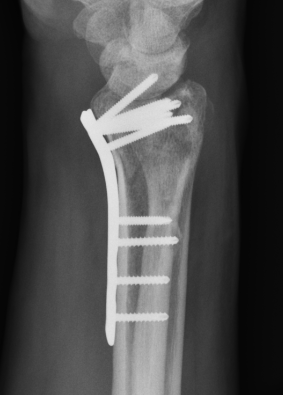

Percutaneous K Wire

Issues

Increased pin site infections

No early immobilization

Technique

Youtube K wire distal radius fracture video

Reduce fracture under anesthesia and fluoroscopy

Radial K wire

- through radial styloid

- can make small incision / blunt dissect to protect branches SRN

- cross fracture site and engage other cortex

- 1.6 or 2 mm K wire

Dorsal K wire Kapandji technique

- percutaneous by hand into fracture site

- tilt distally to reduce dorsal displacement of distal fragment

- drive into proximal radius and engage volar cortex